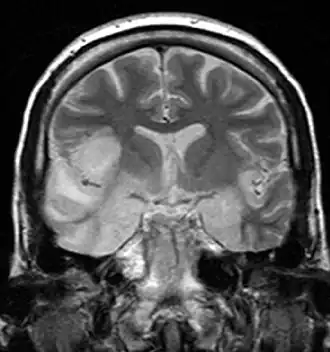

Imagerie cérébrale

L'IRM est considérée comme le gold standard de l'imagerie d'une encéphalite. Elle est anormale dans 90 % des cas d'encéphalite herpétique, mais elle peut être normale dans des cas d'encéphalite auto-immune[7]. Le scanner est moins sensible que l'IRM et donne souvent des résultats normaux dans les premiers jours[4].